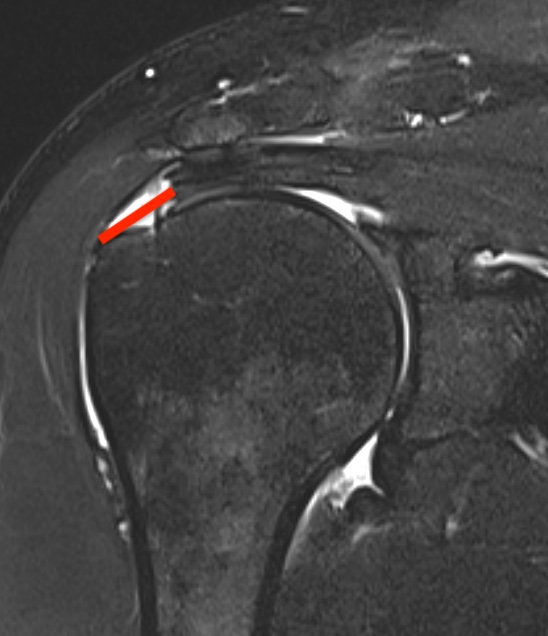

Supraspinatus atrophy

Tangent sign

- sagittal MRI

- line connecting superior coracoid and superior border scapular spine

- if supraspinatus muscle is below line, there is significant atrophy

- positive tangent sign / significant atrophy associated with larger tears / irrepairable tears

Negative tangent / no atrophy Positive tangent / significant supraspinatus atrophy